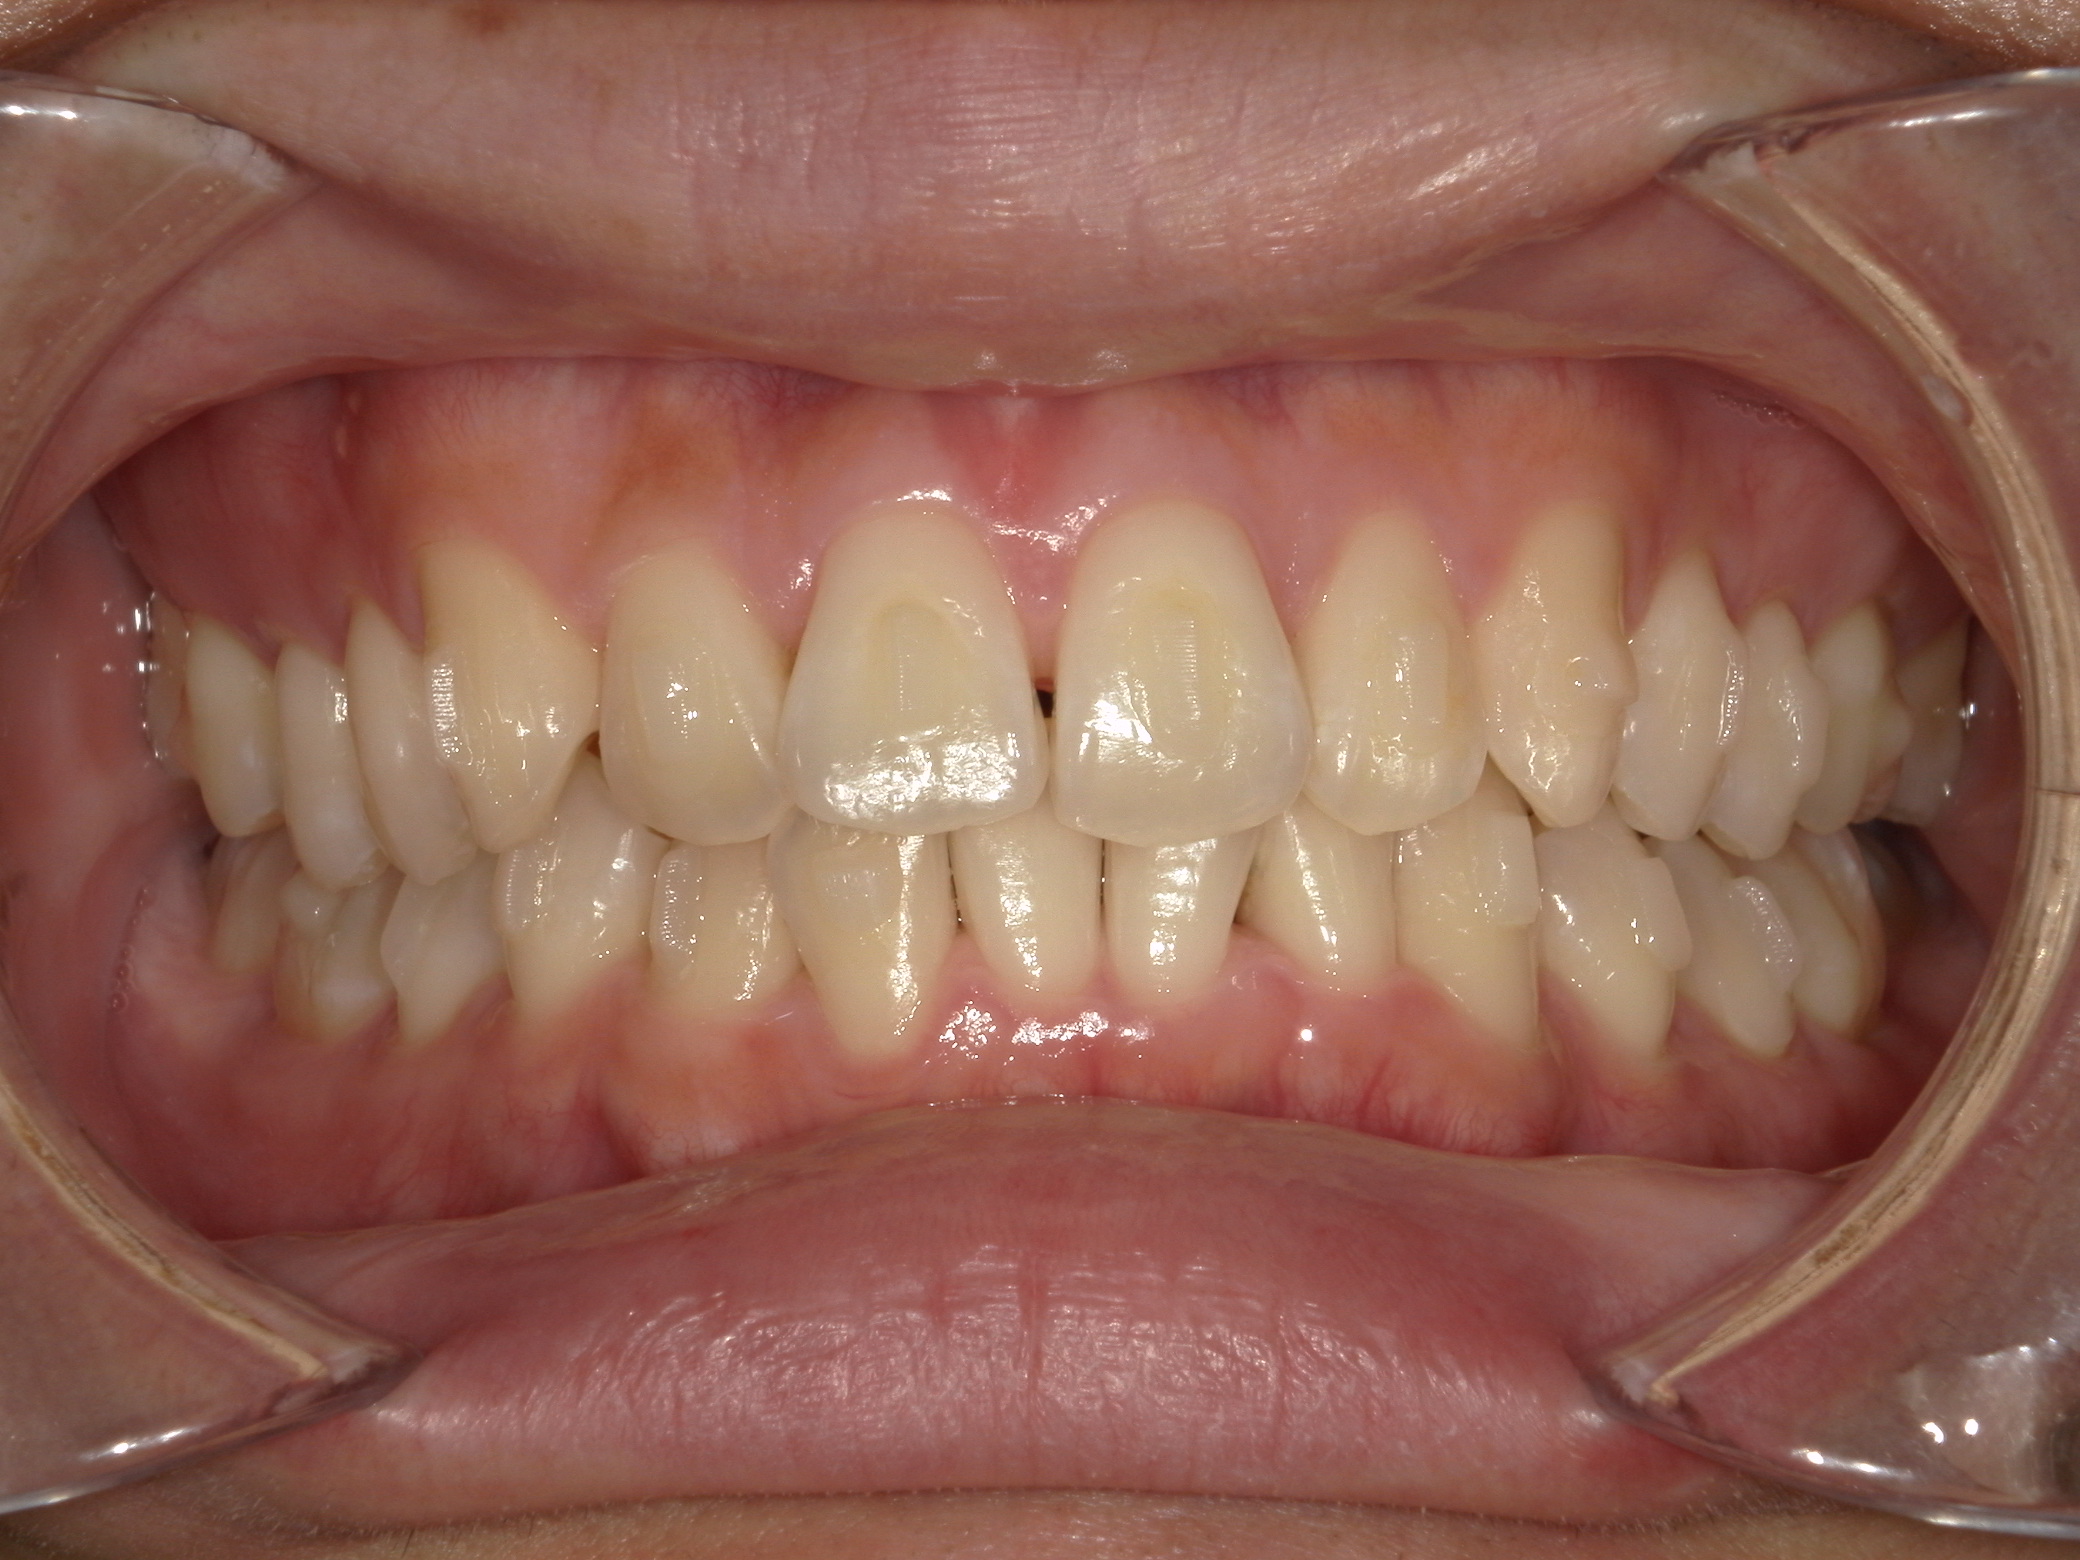

治療前

治療後